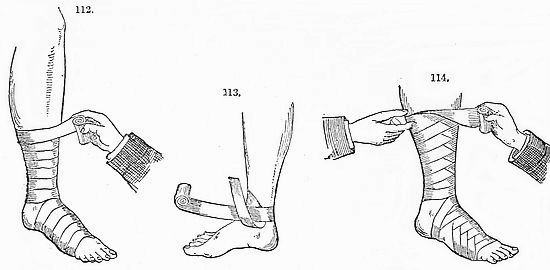

The Sickroom.—The Room; the Nurse; the Bed; Sickroom Accessories; Feeding Patients; Invalid Dishes and Drinks; Administering Physic; Domestic Remedies; Accidents and Emergencies; Bandaging; Burns; Carrying Injured Persons; Wounds; Drowning; Fits; Frostbites; Poisons and Antidotes; Sunstroke; Common Complaints; Disinfection, &c.